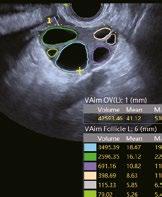

Intelligente Erfassung und Stadieneinteilung von Schilddrüsenerkrankungen

Schilddrüsenknoten werden in Echtzeit oder auf gespeicherten Bildern erkannt, zusammen mit dem T-RADS-Kategorisierungs- und Berichtstool, wodurch die klinische Routine der Schilddrüsenultraschalluntersuchung genauer und aussagekräftiger wird.

Follikel